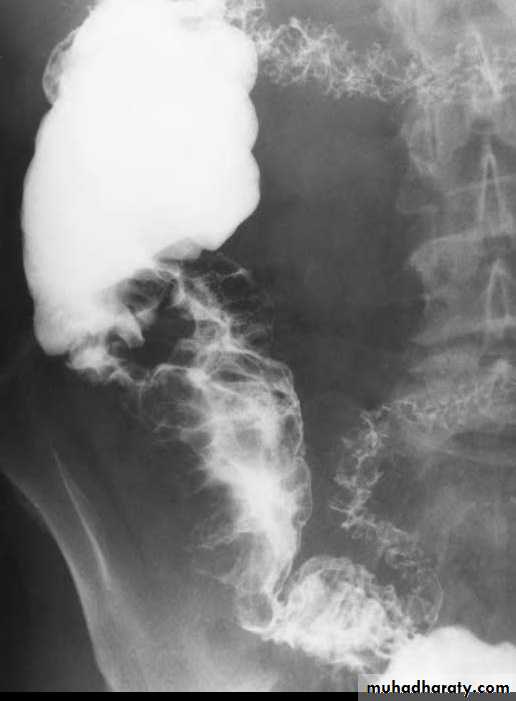

A long segment of narrowed ileum (string sign) is present with proximal ileal dilation& caecal contraction

TI

caecum